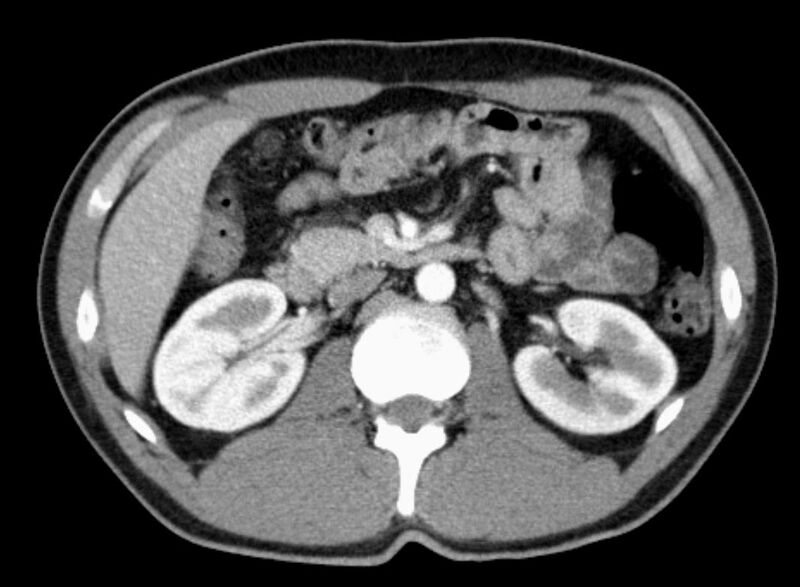

Abdomen (Bauch und Becken)

• Diagnostik von entzündlichen und tumorösen Erkrankungen der Bauchorgane

• Diagnostik von akuten Notfällen wie Darmverschluss, Hohlorganperforation oder Traumafolgen

• Darstellung der großen Gefäße zur Erkennung von Gefäßverschlüssen (z. B. Mesenterial - Arterienembolie oder Einengungen von Gefäßen (z. B. Nierenarterien)

• Darstellung und Therapieplanung von Aneurysmen (CT- Angiographie)

• Virtuelle Kolonographie zur Darstellung des Dickdarmes z. B. bei Kontraindikation zur Darm-Spiegelung oder nur unvollständig durchführbarer Koloskopie.